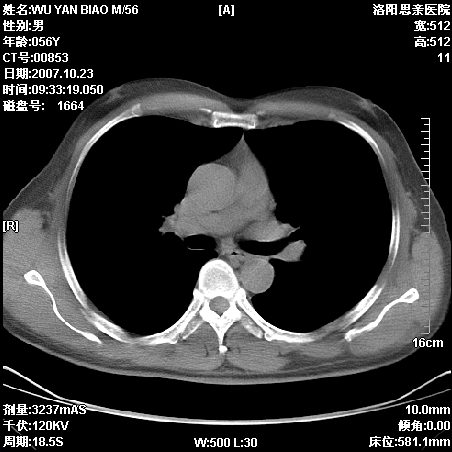

标题: CT10160:M56Y,体检发现,病人无不适,病人随访中 [打印本页]

标题: CT10160:M56Y,体检发现,病人无不适,病人随访中

后上纵隔占位,与肺交界清,宽基底附着脊柱,密度均匀,局部骨质无明确改变.

考虑;神经源性肿瘤,---起源交感n链?,不除外肠源性囊肿.

与纵隔关系密切,密度均匀。只能考虑:后纵隔神经原性肿瘤!

1、病灶在后纵隔脊柱旁沟内,此处是神经原性肿瘤的好发部位

2、病灶边缘光滑整齐,更说明病灶来于纵隔,由于有胸膜的包裹所以才导致这么光滑的边缘

3、病灶内的密度均匀